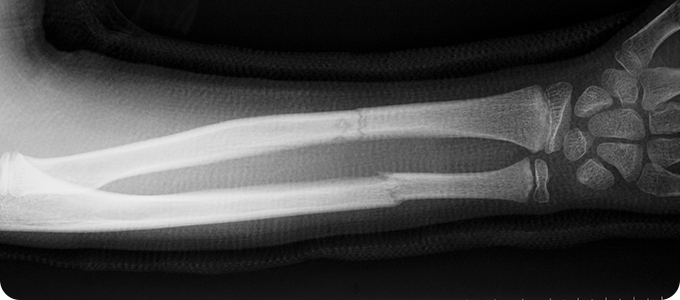

상지골절

• 위팔 골절, 쇄골 골절, 손목 골절은 손을 짚으면서 넘어질 때,

팔을 곧게 뻗은 채로 넘어질 때나, 교통사고, 타박 등에 의해 발생합니다.

골다공증 등으로 인해 뼈가 약해진 분에게 더 쉽게 발생할 수 있습니다.

• 골절이 발생한 부위 주변으로 통증과 압통이 발생하는데,

이 통증은 근육의 경직, 뼛조각의 겹침, 주위 연부 조직의 손상이 원인입니다.

골절 부위가 붓고, 피부 바깥에 보이는 점상 출혈이 발생합니다.

• 골절이 조금이라도 의심된다면 반드시 X-ray 촬영을 시행하여 확인해야 합니다.

부위별로 방향과 각도를 달리하여 여러 장의 X-ray를 찍어서 골절 유무를 확인합니다.